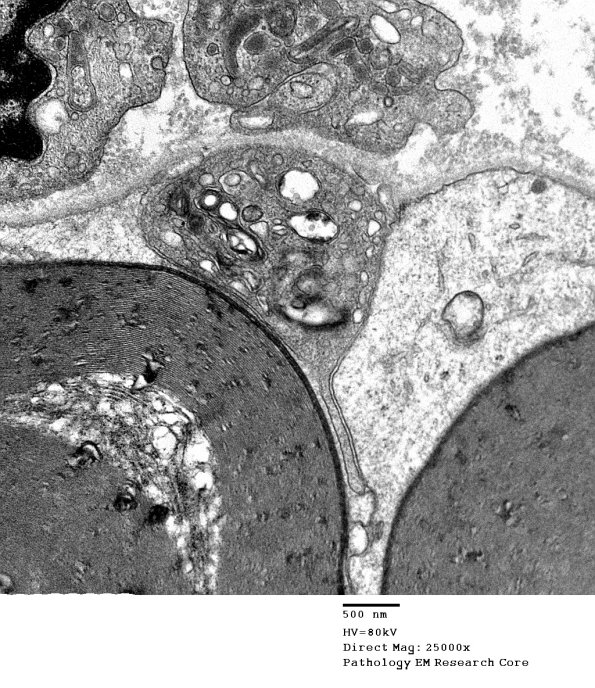

1D14 CIDP (Case 1)  EM 015 - Copy

The macrophages have only begun to work on the myelin. (electron micrograph)